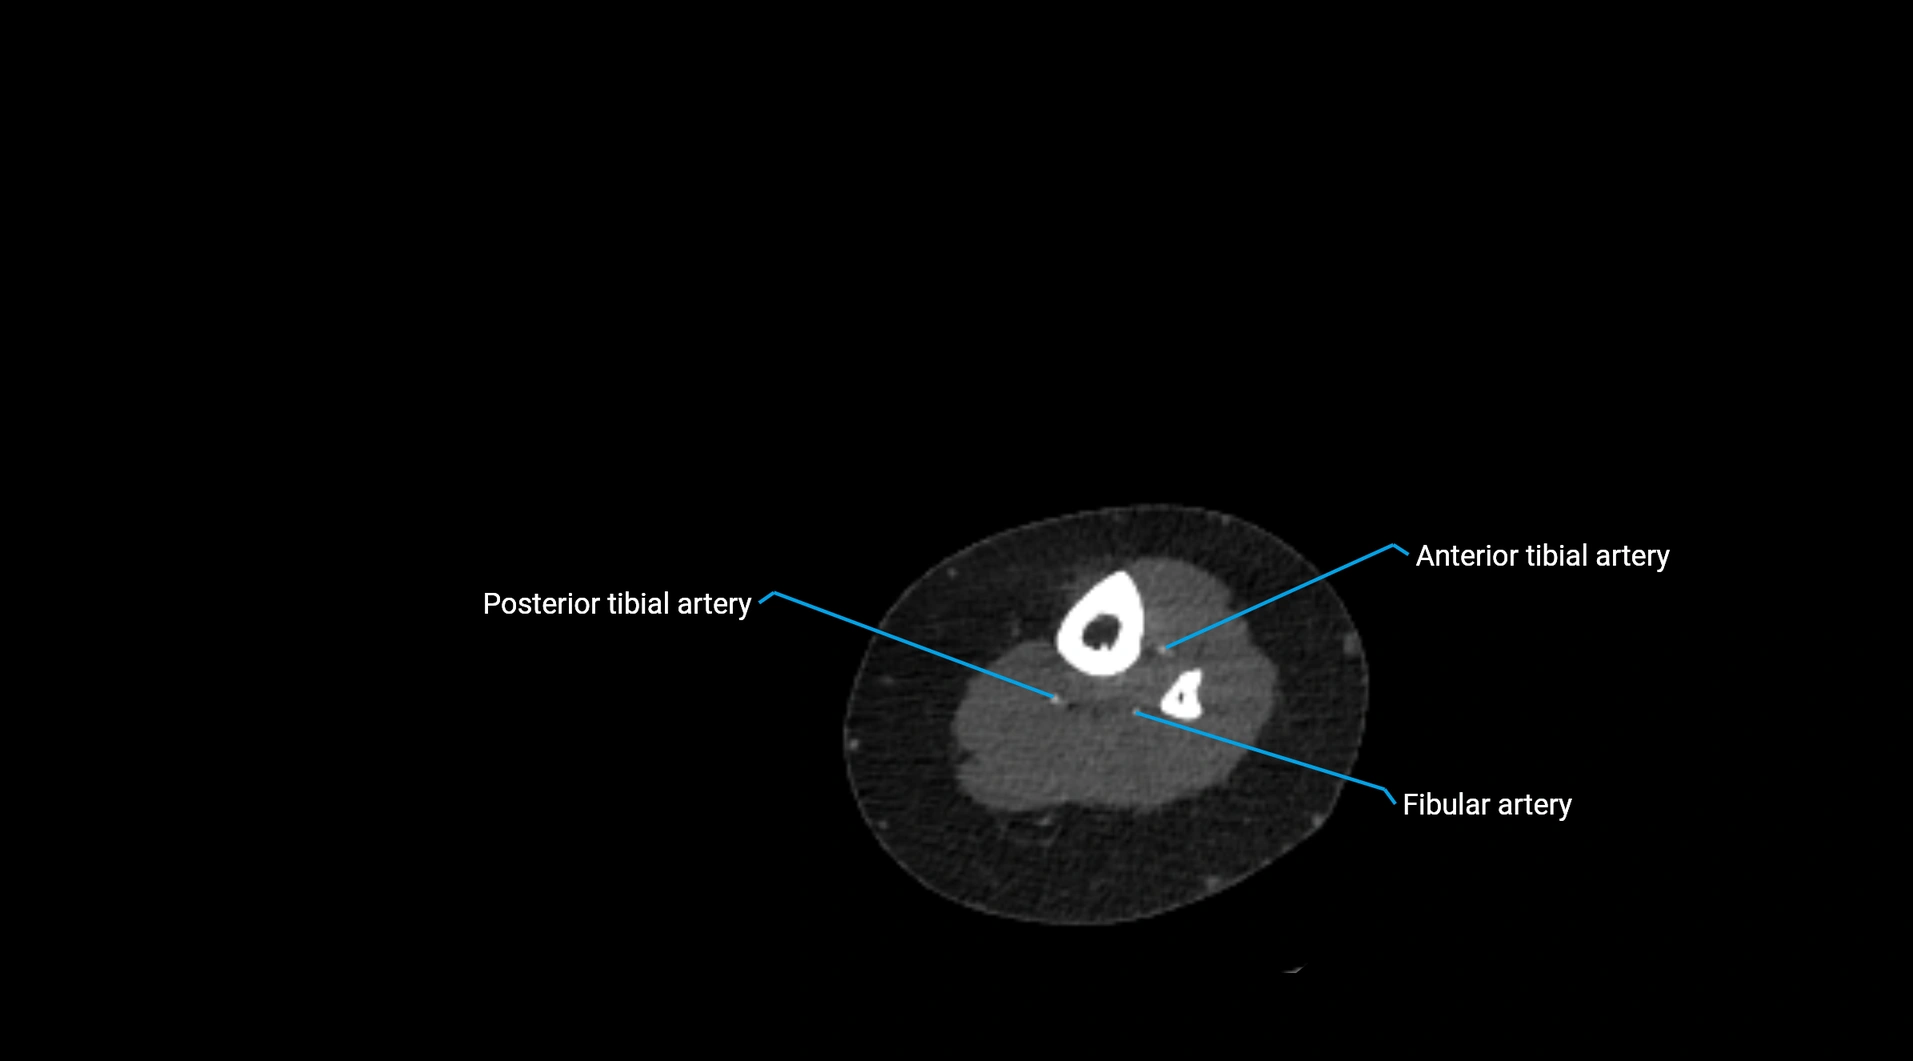

Contrast-enhanced CT (CTA):

• Gold standard for abdominal aortic imaging

• Provides excellent detail of lumen, wall, aneurysm, thrombus, and branch vessels

• Multiplanar and 3D reconstructions help in aneurysm measurement, stent graft planning, and dissection evaluation

• Detects acute rupture, traumatic injury, or occlusion with high sensitivity